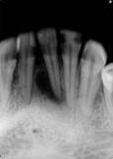

antes depois